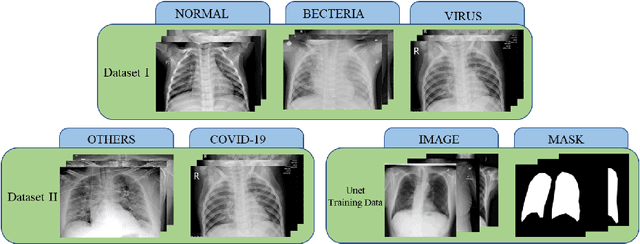

Figure 1 for A cascade network for Detecting COVID-19 using chest x-rays